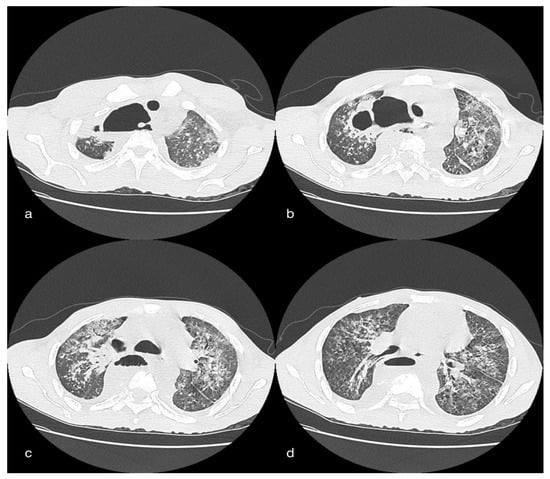

The chest CT showed, bilaterally, the presence of multiple densitometric areoles of the GGO type with predominant subpleural distribution, especially in the slopes, with thickening of the interlobular septa with a “crazy paving” pattern. Three was also widespread ventilation phenomena. Pericentimetric lymphadenomegalies were observed in mediastinum. Visual Score: LSD: 25–50%; LM: 0–25%; LID: 25–50%; LSS: 25–50%; LIS: 25–50%. Abdomen CT revealed, on the anteromedial side of the right thigh, the marked and wide-spread imbibition of the soft tissues due to evidence of contrast medium (arterial) extravasation in correspondence with the anterior side by two collateral branches of the superficial femoral artery, homolateral to the middle III and the III distal as a sign of active bleeding in the lower limb (Figure 4).

Figure 4. A 85-year-old female patient in whom we observe, in the late phases of the study, a marked and diffuse imbibition of the soft tissues on the antero-medial side of the right thigh due to evidence of extravasation of mdc (arterial) in correspondence of the anterior side by two collateral branches of the superficial femoral artery ipsilateral to the middle III and distal III, as well as signs of active bleeding.

Evidence of multiple areoles of GGO-type densitometric increase with associated thickening of the interlobular septa from crazy paving was found in both lungs, predominantly subpleural. There are multiple fibrotic striae with a course parallel to the pleura, more evident in the lower lobes. No significant ilo-mediastinal adenomegalies and no pleural effusion were reported (Figure 6).

Figure 6. A 49-year-old male patient in whom massive invasive ventilation resulted in the formation of pneumomediastinum. The formation of pneumomediastinum is due to traumatic rupture of the alveoli (caused by invasive ventilation), a phenomenon known as the Macklin effect. Subcutaneous emphysema can also be seen.